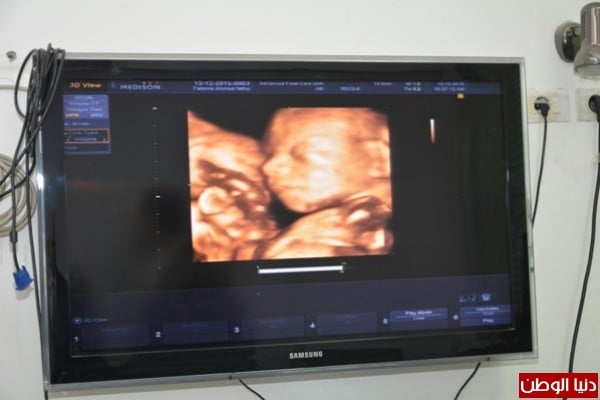

كما يساهم الفحص فى تحديد مسببات نزيف الحمل ومشاكل نمو الجنين وذلك عن طريق إجراء صورة مجسمة رباعية الأبعاد وأشعة متقدمة عن العيوب الخلقية للأجنة وأشعة تشريحية باستخدام أجهزة الوحدة من أجهزة فحص ثلاثي الأبعاد ونبض الجنين وأجهزة دوبلار .